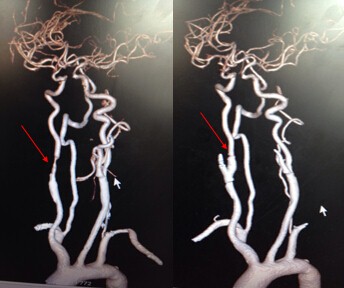

颈动脉内膜剥脱术(CEA)前后血管变化(红色箭头显示血管狭窄解除)